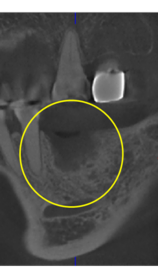

インプラント周囲炎

Perio Wave+Er:YAGレーザー+コールドレーザーの例です。

左の画像が照射前です。3ヶ月でここまで治癒しました。